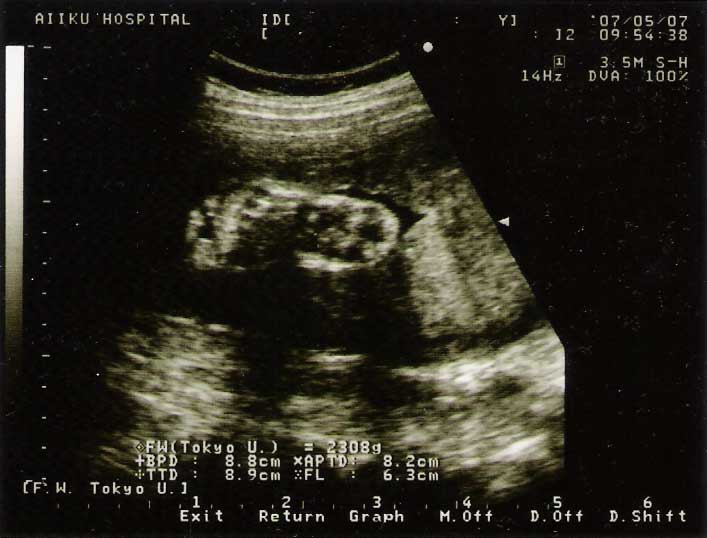

今日はNSTっていうのをやりました。 お腹に色々つけて20分くらい赤ちゃんの心拍数とって様子みる んですけど胎動起きたらボタン押さないといけないんだけど ベットに横になってるから眠くなっちゃってね~あと今日は血液検査したりエコーでサイズはかったり 内診したり(子宮口調べてる時かな?痛かったよ) 今日は、かなり内容の濃い診察で。 サイズ、はかったんだけど少し小さめで2308gでも足が大きいので先生いわく身長があるのかも!?と そうすると身長は推定体重に反映されないから? (結構、推定体重ってアバウトらしい 思えば頭とか胴体、大腿骨のサイズだけだもんね?) もしかすると実際はもう少し体重あるかもとのことで一安心てゆ~か、私も足でかいんだけどお子様もでかいみたいだわ足の裏うちの兄貴も生まれた時、身長がでかかったらしいし・・・ まぁ、カラダもでかかったらしいが。私もだけどそういえば今回で足の裏エコー写真、3枚目なんだけどまぁ、そんなこんなで子宮口の開き具合5ミリとか言ってたカナ? 先生いわく私、安産タイプらしい・・・良かった良かった。 まぁ、体格もいいからね~そんなこんなで順調な感じの経過らしく、でも予定日の 29日あたりだと陣痛がきてしまうのでその前の週と言う事で 旦那の希望通りの日にちに決めてきました。 (計画無痛分娩をするので)入院が21日で22日に出産予定です。 あと2週間後です~ドキドキです。 入院前に陣痛来ない事を祈ります。 赤ちゃんに毎日お願いしておこうと思います 今回の健診費用 16720円

2007年05月07日